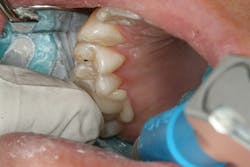

The clinical case in Figure 3 illustrates a patient who presented with a large, failing restoration containing cracks and decay. The patient was interested in an all-ceramic restoration. Occlusion was checked with articulating paper prior to treatment with a CAD/CAM restoration (figure 4). All previous restorative materials were removed from the tooth (figure 5). The tooth was restored using Grandio Core Dual Cure (Voco) build-up material (figure 6). A crown preparation was completed for a chairside CAD/CAM crown using the CEREC system (Dentsply-Sirona). The material of choice for this restoration was IPS e.max CAD (Ivoclar Vivadent), which is seen in Figure 7 after milling and in precrystallization form. The restoration was tried in and then polished, glazed, and placed in the oven for crystallization. The internal surface was then etched with 4.9% hydrofluoric acid, rinsed, and then coated with a silane coupler to create an optimal surface for bonding with the resin luting agent. The tooth was isolated and cleaned prior to etching. Once etched, the adhesive bonding agent (Futurabond U) was activated to mix the two liquids within the single-dose blister package. The blister seal was broken with the bonding agent brush and the adhesive was applied and agitated for 20 seconds. The adhesive was lightly dried for five seconds and then cured with an LED curing light for 10 seconds. A dual-cured adhesive resin luting agent (Bifix QM) was dispensed into the crown with its automix syringe (figure 8). The crown was seated and excess cement was removed after a two-second light cure. The tooth was then flossed and occlusion was checked (figure 9). The patient was very satisfied with the final result.

Figure 5: Teeth after all previous restorations have been removed

Figure 6: Teeth after restoration with Grandio Core Dual Cure build-up material (Voco)